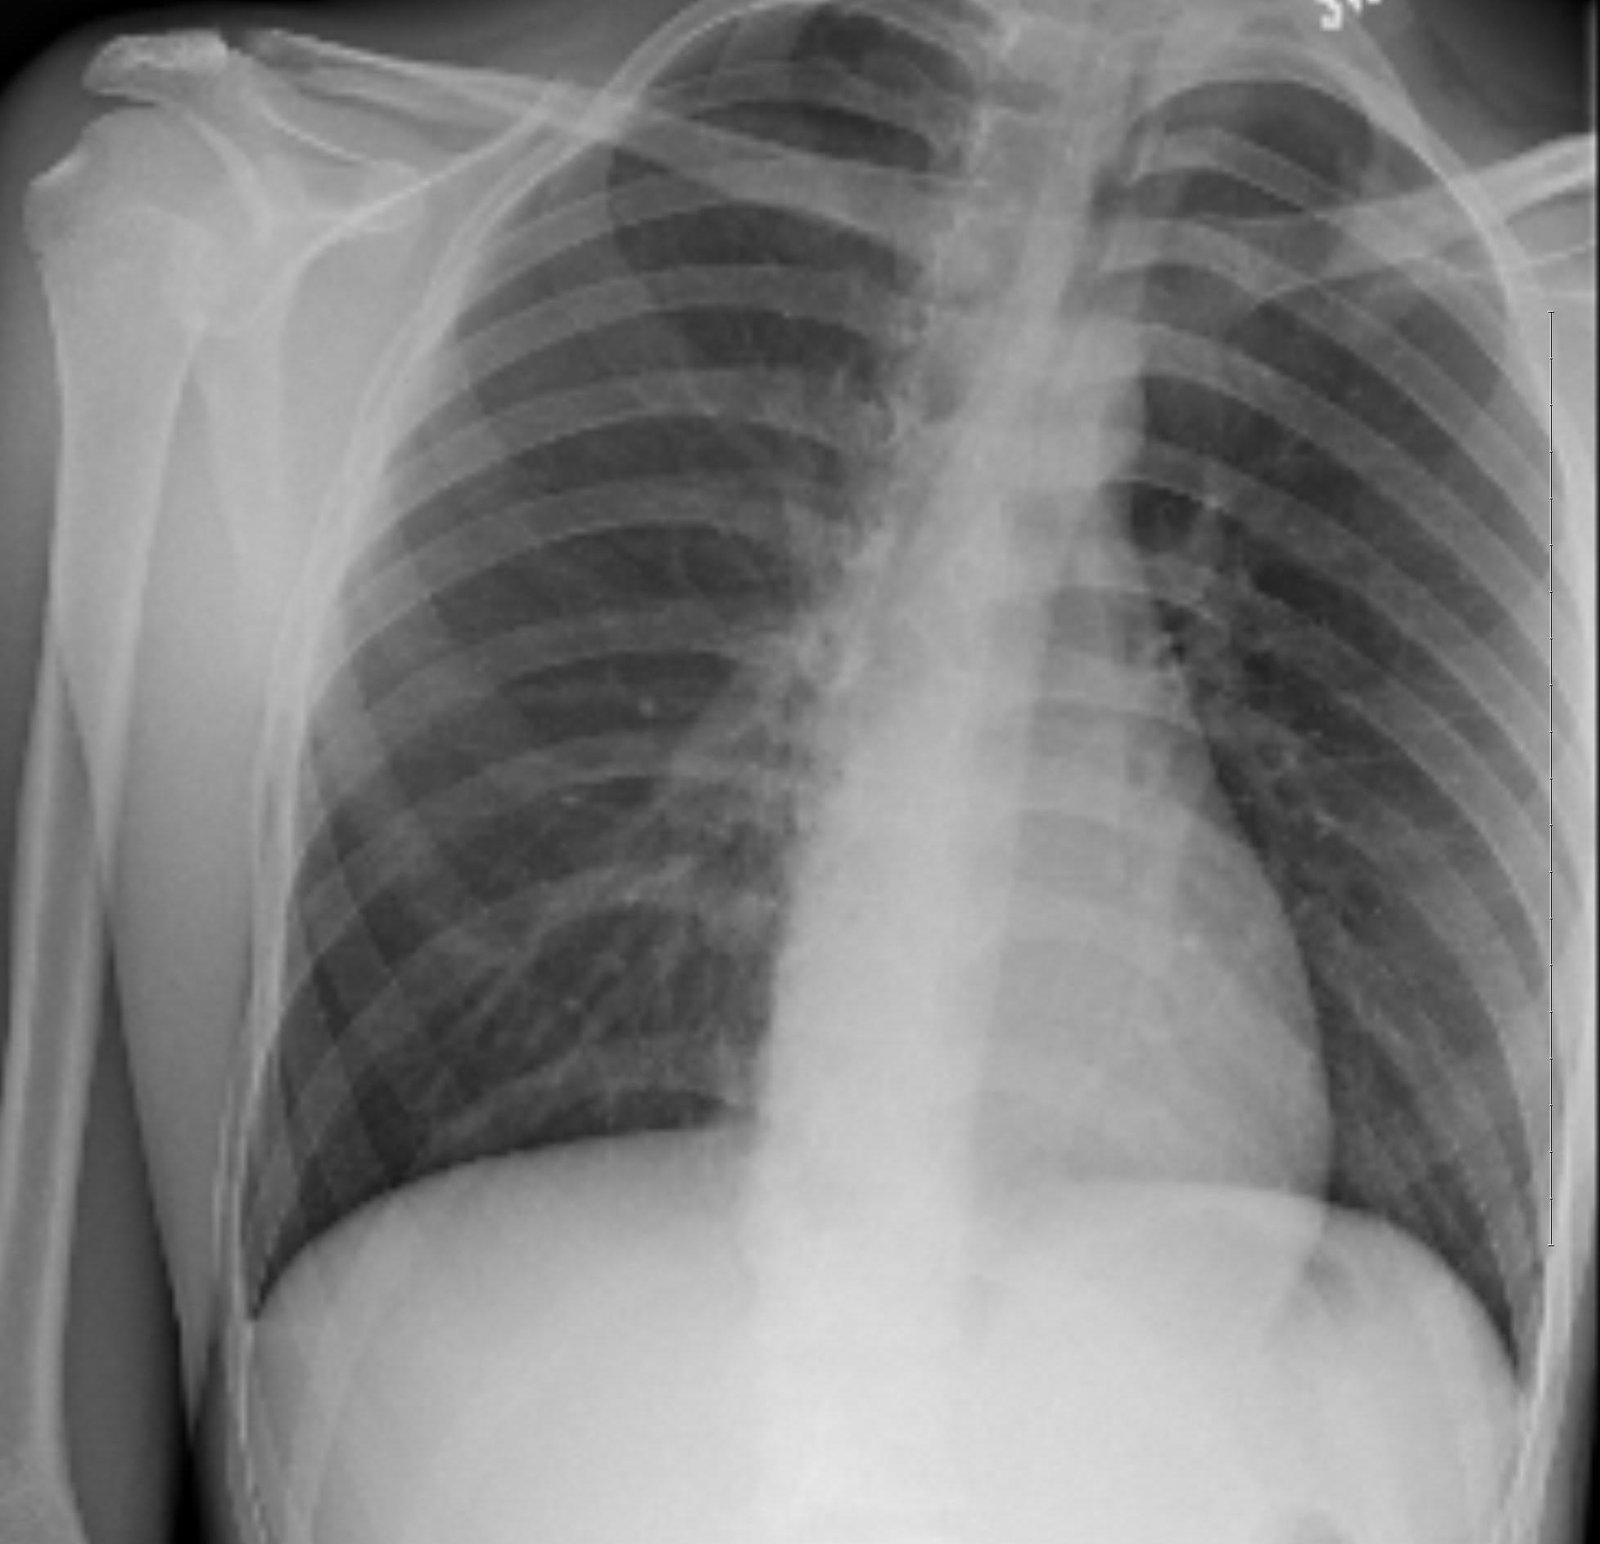

A 16-year-old male with asthma was brought to the emergency department by his parents for increasing right-sided chest pain associated with cough and mild dyspnea over the past week. Albuterol inhaler did not provide relief. He denied recent trauma, fever, sweats, and chills. The patient’s vitals and oxygen saturations were stable. Physical exam revealed a tall, slender body habitus with no signs of chest wall injuries. Bilateral breath sounds were present, but slightly diminished on the right. A chest radiograph was ordered to determine the etiology of the patient’s symptoms.

Significant findings:

Initial chest radiograph showed a 50% right-sided pneumothorax with no mediastinal shift, which can be identified by the sharp line representing the pleural lung edge (see arrows) and lack of peripheral lung markings extending to the chest wall. While difficult to accurately estimate volume from a two-dimensional image, a 2 cm pneumothorax seen on chest radiograph correlates to approximately 50% volume.1 The patient underwent insertion of a pigtail pleural drain on the right and repeat chest radiograph showed resolution of previously seen pneumothorax. Ultimately the pigtail drain was removed and chest radiograph showed clear lung fields without evidence of residual pneumothorax or pleural effusion.